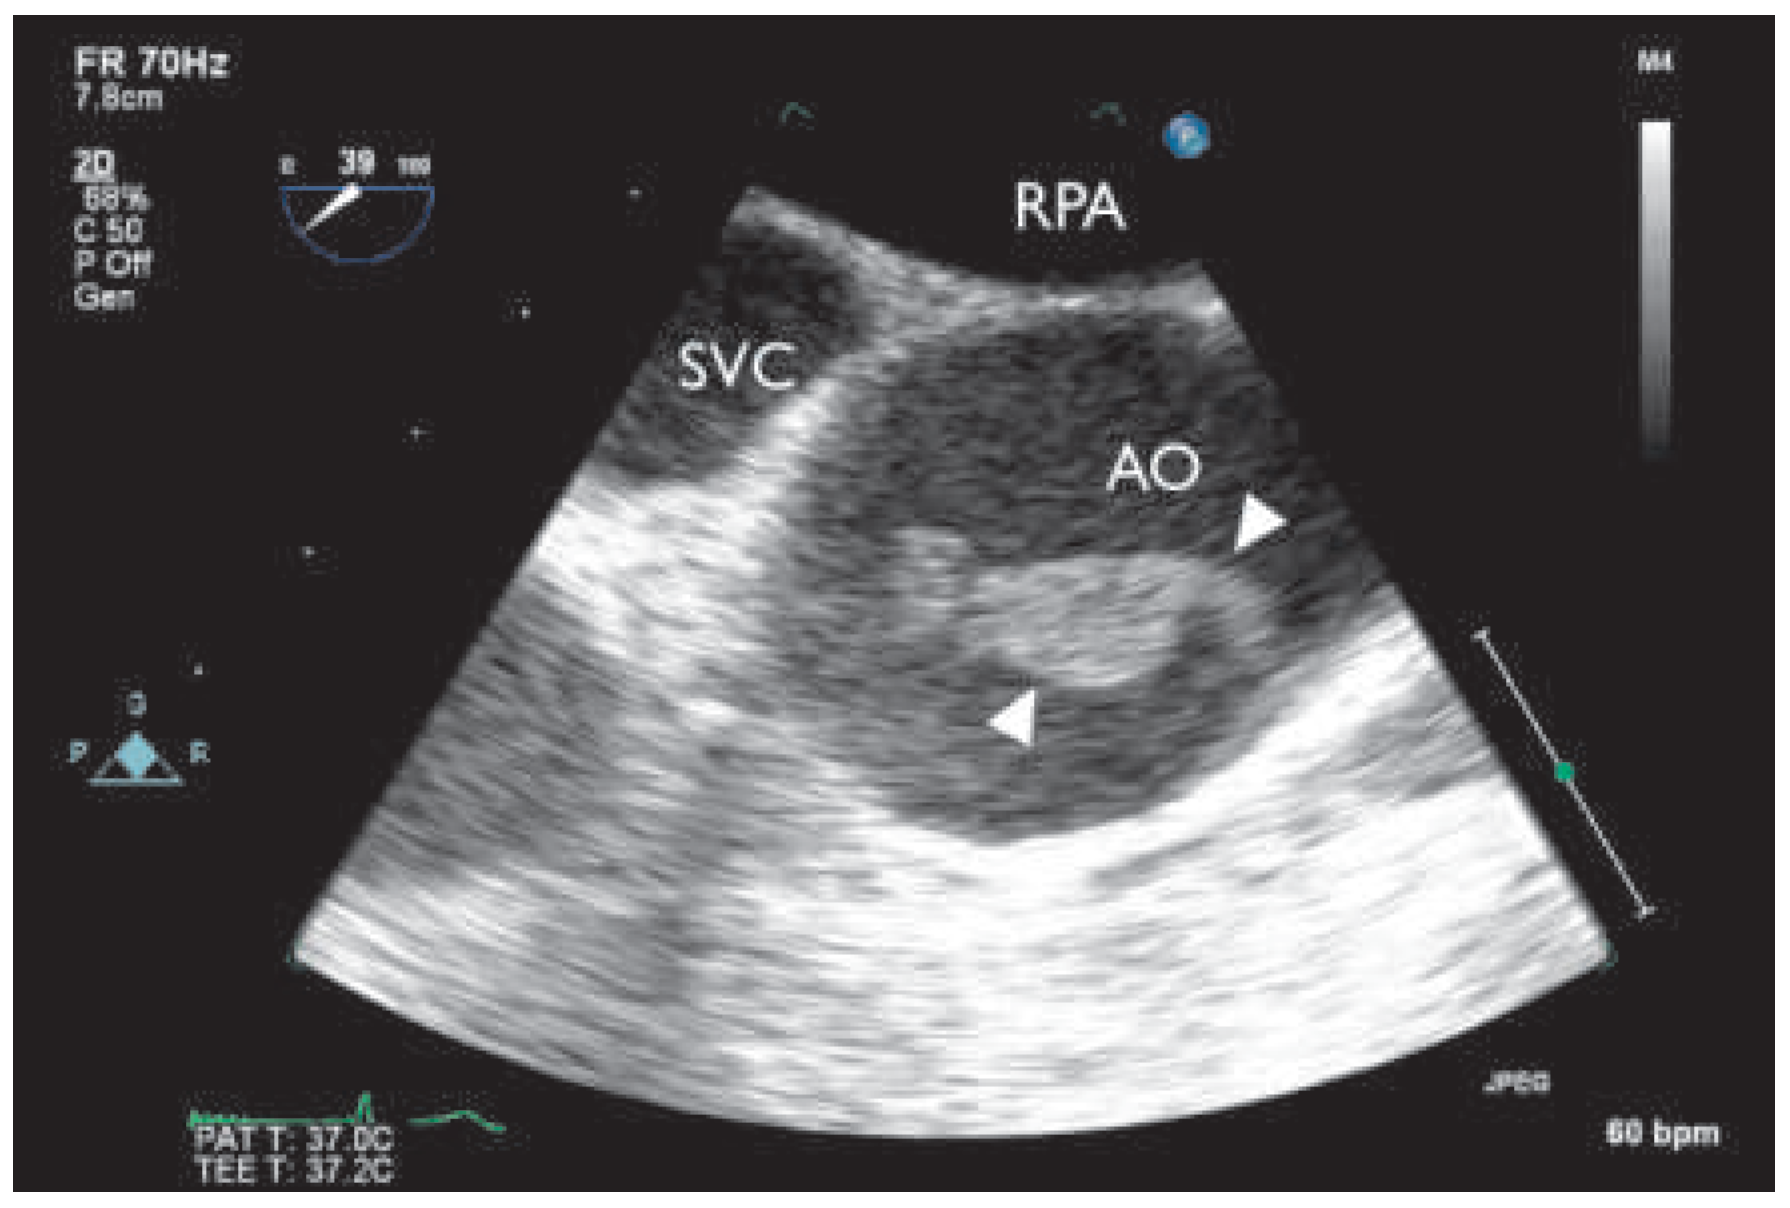

During the search for an embolic source, transthoracic echocardiography finally revealed three unusual structures in the ascending part of the aortic arch. The patient was further evaluated with transoesophageal echocardiography, which showed highly mobile structures within the ascending aorta (Figure 1 and Figure 2). One insertion site to the slightly thickened anterior aortic wall was detected approximately 4 cm distal to the aortic valve. Intracardiac thrombi could be excluded.

Figure 1. Multiplane transoesophageal echocardiography (39°), thrombus (indicated by white triangles) with attachment to the anterior aortic wall (short axis). AO = ascending aorta; RPA = right pulmonary artery; SVC =superior vena cava.